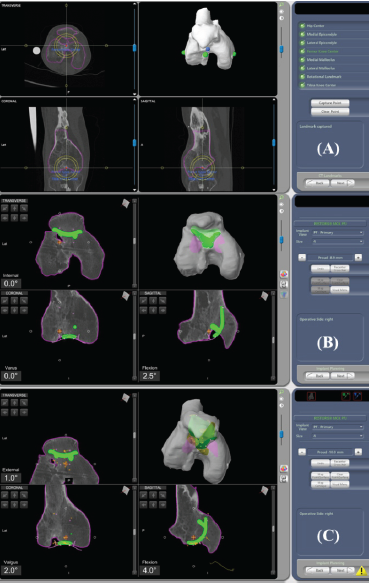

The patient exhibited joint space narrowing in the medial compartment of the knee on radiographs; however, on magnetic resonance imaging (MRI), there was only minimal cartilage thinning (Fig. 1). Notably, a skyline patella view radiograph could not be obtained due to the existing deformity. We ruled out the possibility of infections since the total count and inflammatory markers were within the normal range, and the MRI showed no signs of infection. Given the distorted anatomy, RA-PFA using the MAKO Robot (Stryker, USA), complemented by a quadriceps-plasty procedure, was planned. 3D-CT scan was performed to facilitate precise pre-operative planning. A MAKO product specialist segmented the scans using the MAKO planning software. Since the patella was ankylosed, the patella and femur were taken en bloc for segmentation, unlike regular cases (Fig. 2).

Figure 2: (a) Segmentation of femur and patella en bloc, (b) Pre-operative plan of the trochlear component size and position, (c) Implant position virtually adjusted.

Implant size and positioning were planned pre-operatively on the 3-D CT scan (Fig. 2). On the transverse plane, the largest trochlear implant was used without overhang, and in the sagittal plane, the implant tip was anterior to Blumensaat’s line. On the coronal view, the component was centered on the notch. Varus/valgus, flexion/extension, and external/internal rotation were adjusted as necessary within the recommended safe zone [8].

Implant position was virtually adjusted for a seamless transition from the component to the mapped trochlear surface after registration (Fig. 2). Subsequently, the preparation of the femoral trochlea was undertaken using the robotic arm’s burr, cutting through the remaining portion of the resected patella to access the true trochlea (Video 4: Trochlear preparation using robotic arm’s bur.).